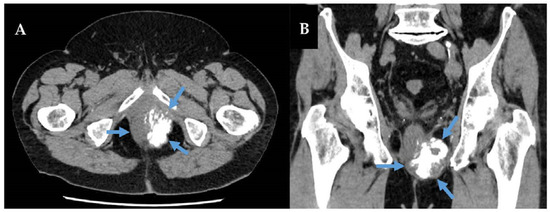

- Yim, H.; Tang, Y.L.; Tandon, A.A. Multifocal Retroperitoneal and Pelvic PEComas Mimicking Liposarcoma: A Case Report and Review of Literature. Radiol. Case Rep. 2021, 16, 2624–2629. [Google Scholar] [CrossRef]